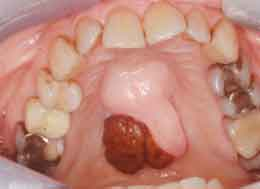

I was the only dental hygienist in a large lecture hall filled mostly with oral surgeons who were grappling with comanagement and prevention strategies for patients who are at risk of drug-induced osteonecrosis of the jaws (DIONJ). The guest faculty presenters (Robert Marx, DDS, and Richard Kraut, DDS) continued to roll out case studies of individuals (horrifying images of necrosed maxillas and mandibles) who fell victim to these offending drugs.

Most of the time, DIONJ associated with an oral bisphosphonate or denosumab can be effectively managed with 0.12% chlorhexidine and an intermittent course of systemic antibiotics along with a drug holiday alone or followed by surgery.2 The University of Miami database finds a 50% resolution rate for DIONJ with a drug holiday of nine months alone.2 About 40% of subjects required alveolar debridement/local alveolar resection with a nine-month drug holiday.2 Ten percent required a continuity resection of the mandible or a partial submucosal maxillary resection and a sinusostomy after a nine-month holiday consideration. Drs. Marx and Kraut also use a test called CTX that assesses the level of bone resorption. Serum cross-linked C-telopeptide of type I collagen (CTX) is a marker of osteoclastic activity.5 It is still unknown at this time whether or not this particular test can predict the risk of developing DIONJ.5